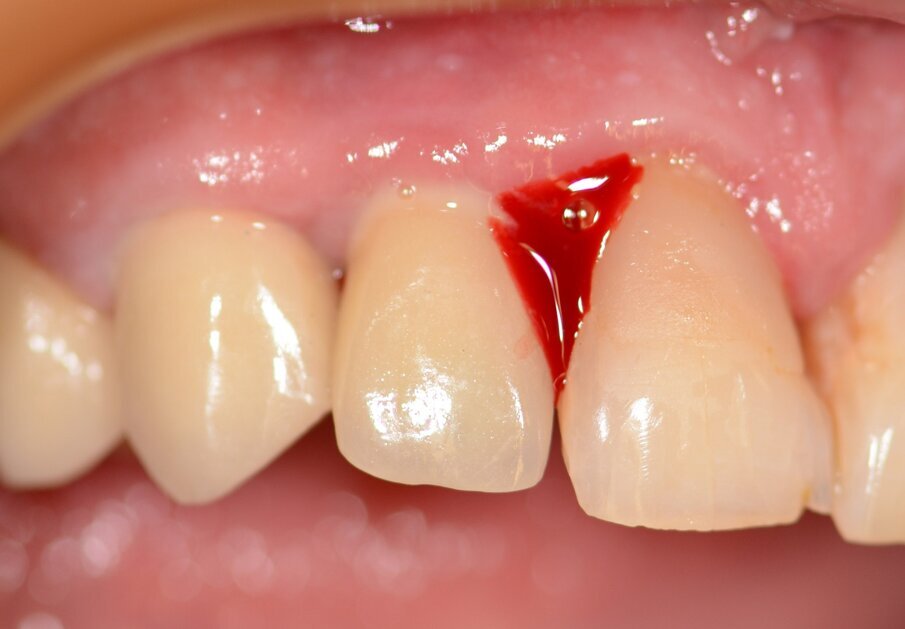

Case 1 was a patient who presented with deep pockets (9 mm), bleeding on probing and visible purulent effusion (Figs. 1–7) and was treated with a non-surgical protocol.

Fig. 1: Initial situation.

Fig. 3: Bleeding on probing.